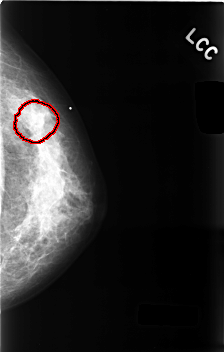

FILE: C_0494_1.LEFT_CC.OVERLAY

TOTAL_ABNORMALITIES 1

ABNORMALITY 1

LESION_TYPE MASS SHAPE OVAL MARGINS OBSCURED

ASSESSMENT 3

SUBTLETY 1

PATHOLOGY BENIGN

TOTAL_OUTLINES 1

BOUNDARY